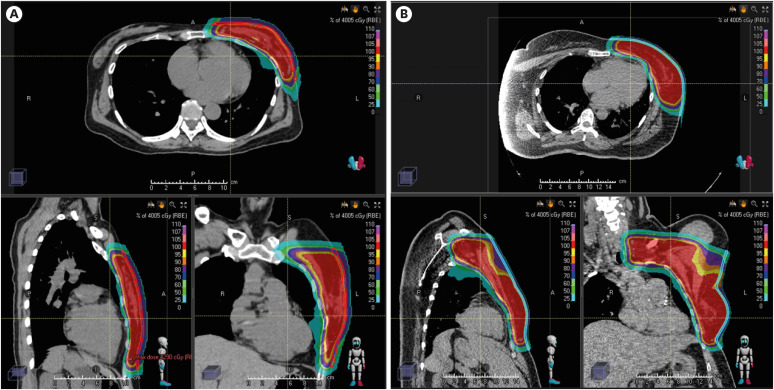

目的:铅笔束扫描(PBS)是质子束治疗(PBT)中使用的一种现代传输技术,可减少正常组织的反应。目前还没有关于乳腺癌皮炎与铅笔束扫描之间剂量学相关性的报道。本研究旨在调查使用 PBS 进行 PBT 的乳腺癌患者发生 2 级或以上皮炎的相关因素:回顾性分析了在 2019 年 12 月至 2023 年 9 月期间接受辅助放疗的 42 名乳腺癌患者的医疗数据。所有患者均接受了低分次放疗(HFRT),26 Gy(相对生物效应[RBE])/5次分次或40.05或43.5 Gy(RBE)/15次分次,用于整个乳房/胸壁,伴或不伴结节照射。急性放射性皮炎的持续时间定义为放疗开始后 90 天内。采用 Kaplan-Meier 法和 Cox 比例危险模型对 2-3 级皮炎的精算率进行单变量和多变量分析:分别有22名(52.4%)和20名(47.6%)患者被诊断为1级和2级皮炎。多变量分析显示,临床靶体积 (CTV) ≥ 320 cc (p = 0.035) 和皮肤剂量 D10cc ≥ 38.3 Gy (RBE) (p = 0.009) 是导致 2 级皮炎的独立因素。CTV和D10cc均高、高或不高的患者10周累计2级皮炎发生率分别为88.2%、39.4%和8.3%(p < 0.001):据我们所知,这是第一项关于使用 PBS 进行低分量 PBT 的乳腺癌患者皮炎剂量相关性的研究。在 HFRT 时代,使用 PBS 调节皮肤剂量可能会降低皮炎的发病率。

Methods: The medical data of 42 patients with breast cancer who underwent adjuvant radiotherapy between December 2019 and September 2023 were reviewed. All patients received hypofractionated radiotherapy (HFRT), either 26 Gy (relative biological effectiveness [RBE])/five fractions or 40.05 or 43.5 Gy (RBE)/15 fractions, for the whole breast/chest wall with or without nodal irradiation. The duration of acute radiation dermatitis was defined as within 90 days from the start of radiotherapy. The Kaplan-Meier method and Cox proportional hazards model were used for univariate and multivariate analyses of the actuarial rates of grade 2-3 dermatitis.

Results: Twenty-two (52.4%) and 20 (47.6%) patients were diagnosed with grade 1 and 2 dermatitis, respectively. Multivariate analysis revealed a clinical target volume (CTV) ≥ of 320 cc (p = 0.035) and a skin dose of D10cc ≥ 38.3 Gy (RBE) (p = 0.009) as independent factors of grade 2 dermatitis. The 10-week cumulative grade 2 dermatitis rates were 88.2%, 39.4%, and 8.3% (p < 0.001) for patients with both high, either high, and neither high CTV and D10cc, respectively.

Conclusion: To the best of our knowledge, this is the first study on dosimetric correlations for dermatitis in patients with breast cancer who underwent hypofractionated PBT using PBS. In the era of HFRT, skin dose modulation using PBS may reduce the incidence of dermatitis.